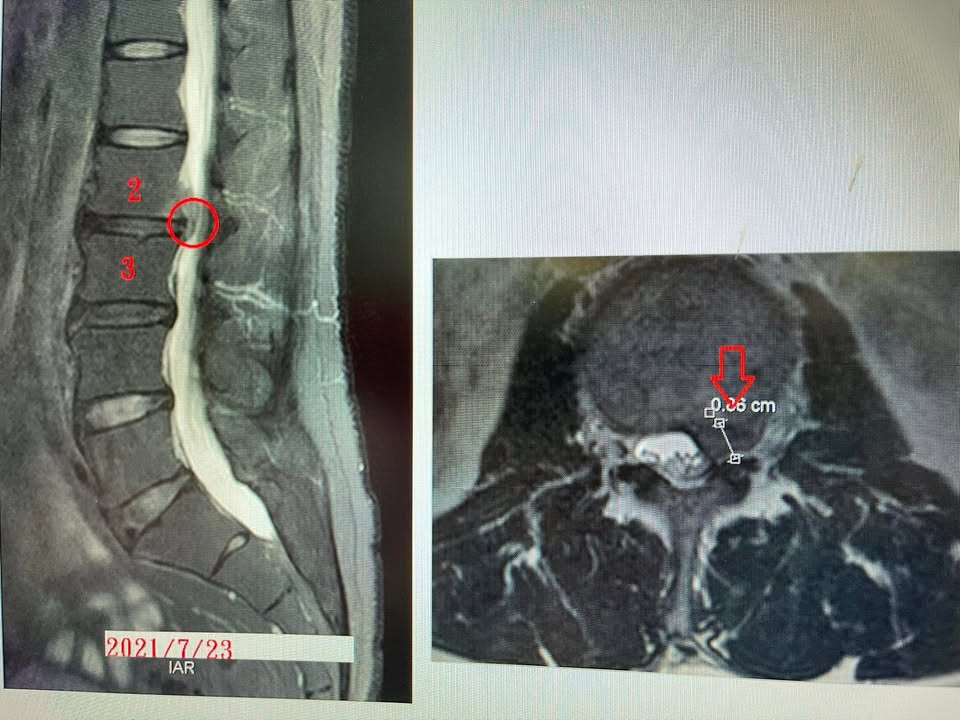

Cervical Spine Treatment Cases 腰椎治療案例 #腰椎滑脫合併椎管嚴重狹窄醫案 #感謝台中市北屯區呂阿姨熱情見證 #原本腰腿疼痛到快... 2022.01.04 #八十老翁腰椎手術兩次仍然不理想 #治療前無法在忠孝東路走超過一分鐘 #忠孝復興交會... 2021.12.29 感謝台看過四家復健科、骨科、醫學中心、整骨,依然效果不如預期,右腳依然麻痛到不行... 2022.02.18 #腰椎滑脫合併嚴重椎管狹窄醫案 #兩個醫學中心骨科醫師都建議開刀 #感謝基隆市信義區... 2021.12.22 ⭕️下背手術失敗綜合症候群 🔲腰椎做過一手術切除骨刺 ‼️半年後又開始復發了 ✳️晨起疼... 2022.01.29 🔎腰椎滑脫心酸血淚史 ‼️原本右腳無法走路合併膝蓋痠軟無力 ✅治療六週徹底改善所有症... 2021.12.14 #腰椎間盤巨大突出脫垂 #原本預計下周要開刀了 #最後真的逆轉勝 #來診前已經痛到無法... 2022.01.29 ‼️巨大椎間盤突出脫垂大痛到無法走進診間 ★醫學中心神外醫師認為可能要開刀 ㊣脊椎整... 2022.01.20 #嚴重的頸椎壓迫導致下肢走路無力 #頸椎整合中醫微創療法逆勝 #頸椎壓迫還會導致腳部... 2021.12.04 ⭕️嚴重椎管狹窄治療醫案 ⁉️將近快半年的疼痛到後來已經快無法走路 ❌走路嚴重跛行何必... 2021.12.09 #天才年輕賽車手巨大椎間盤突出 #之前八周治療完全逆轉勝康復 #提供治療前後核磁共振... 2021.12.02 #上位腰椎L2L3椎管嚴重狹窄案例 #之前痛到無法工作上班快兩個多月 #卡通圖一張秒懂何... 2021.12.01 #腰椎管狹窄一定要急著做手術嗎 #當初痛到走路無法超過二十分鐘 #兒子上網遍尋醫師... 2021.11.26 ⭕️下背手術失敗綜合症候群 🔲腰椎做過三次手術打了五組鋼釘子 ‼️右腳疼痛到連坐輪椅都... 2021.11.25 #感謝台北市文山區蔡先生熱情見證 #右腳痠麻脹痛到嚴重影響日常生活 #腰椎整合微創筋... 2021.11.18 ← 上一頁 5 6 7 8 9 下一頁 →